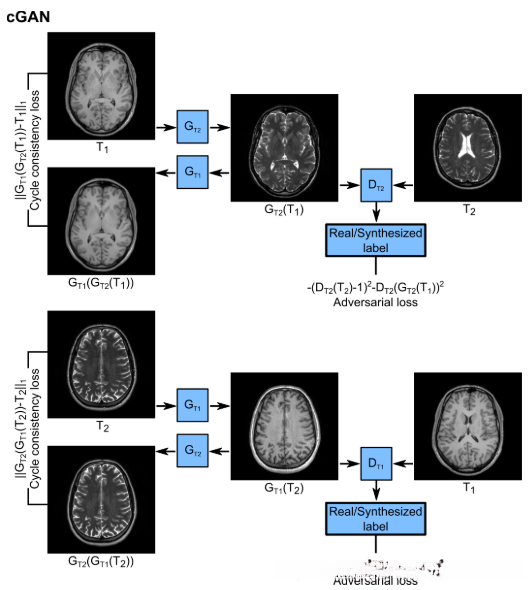

本文提出了一种基于生成性对抗网络(GAN)结构的多对比MRI图像合成新方法。对抗性损失函数最近已被证明可用于各种医学成像应用,并能可靠地捕获高频纹理信息。在跨模态图像合成领域,重要的应用包括CT到PET合成、MR到CT合成、CT到MR合成等等。在这一成功的启发下,我们引入条件GAN模型来从单个模态上合成不同的对比图像,并在正常人和胶质瘤患者的多对比脑部MRI上进行验证 。为了提高精度,该方法还利用了三维影像中相邻横截面的相关信息 。当多对比度图像直接在空间上进行了配准(pGAN)和当它们未进行配准(cGAN)时,我们提供了两种实现方式。对于第一种情况(已配准),我们训练在合成图像和真实图像(如下图所示)之间具有逐像素损失和感知损失的pGAN。对于第二种情况(未配准),我们在用循环一致性替换逐像素损失后训练cGAN ,循环损失增强了从合成的目标图像中重建原始图像的能力(如下图所示)。对正常人和胶质瘤患者的多对比度MRI图像(包括T1和T2加权)进行了广泛的评估。与目前最先进的方法相比,该方法在多对比度磁共振成像合成中获得了定性和定量的精度增强。

用于未配准的图像合成的cGAN模型示意图,基于cycleGAN的框架。